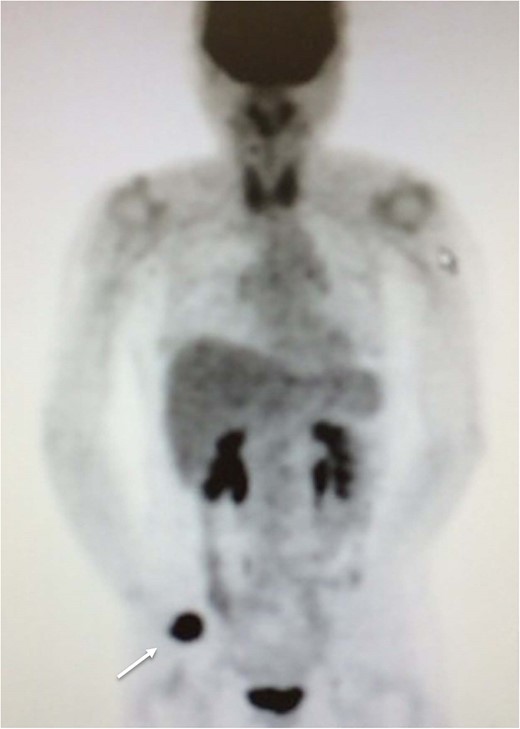

Fifteen months after surgery, the patient presented with redness, pain, and swelling of the right thumb. Radiography revealed right metacarpal bone destruction (Fig. 1). Technetium-99m HDP bone scintigraphy showed strong tracer accumulation in the right thumb (Fig. 2). T1-weighted magnetic resonance images revealed a mass lesion with a contrast effect (Fig. 3). Fluorine-18 fluorodeoxyglucose positron emission tomography also showed abnormal uptake in the right metacarpal bone, with no accumulation at other sites (Fig. 4). Lung and abdominal computed tomography scans showed no distant metastases or recurrence of the primary lesion, and serum tumor marker levels were normal.

Fluorine-18 fluorodeoxyglucose positron emission tomography image depicting abnormal uptake in the right metacarpal bone (arrow), but no accumulation at other sites.